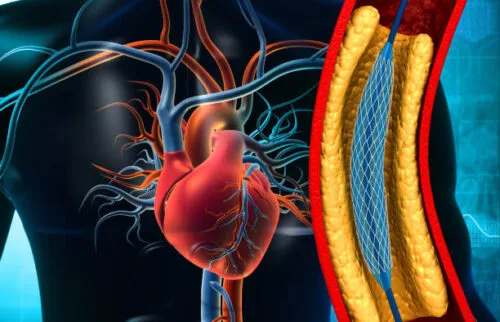

- گرفتگی رگ ها

- بیماری عروق محیطی

- چربی خون بالا

- توصیه های پیشنهادی برای کاهش چربی های خون

- انسداد شریانهای اندام تحتانی(PAD)